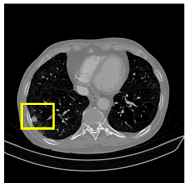

Experiment 3: Clinical Validation on Real-World CT Data

To assess clinical applicability, the model was validated on MEF-PN35—a real-world dataset comprising 804 CT slices from 35 patients with diverse nodule morphologies. Performance was evaluated using the Dice score, sensitivity, specificity, and Miss Rate. Additionally, Grad-CAM visualizations were employed to interpret attention consistency, offering qualitative insights into the model’s focus on lesion regions in realistic clinical scenarios.

This section quantitatively evaluates the segmentation efficacy of CAAF-ResUNet across three boundary-aware loss configurations using the MEF-PN35 dataset, which consisted of 804 CT slices obtained from 35 patients at the University Medical Center Ho Chi Minh City. The results are summarized in Table 8, while Figure 3 illustrates the patch-wise distribution of Dice scores under three different boundary-aware loss configurations.

3.4.2. Representative Cases with Segmentation Challenges on the MEF-PN35 Dataset

To complement the quantitative evaluation, we present a set of representative cases from the clinical dataset that exhibited typical segmentation challenges. These cases were selected to reflect diverse morphological characteristics observed in pulmonary nodules, such as spiculated boundaries, small size, vessel adherence, pleural attachment, cavitation, and clear isolation. Rather than aiming for exhaustive categorization, our intent is to highlight a range of practical difficulties encountered in real-world scenarios and to qualitatively assess how different boundary-aware loss functions respond to these variations. Each challenge is labeled (C1) through (C5) in Table 10 and is consistently referenced in the corresponding detailed illustrations that follow.

Following the summary in Table 11, we present detailed visual comparisons for selected representative cases, each corresponding to a specific segmentation challenge. These cases are consistently labeled using the Challenge ID (CID) codes defined in Table 9 to facilitate cross-referencing between the summary and the case illustrations. Each table reports segmentation results across three loss configurations (Sobel, Laplacian, and Hausdorff) using five columns. Loss indicates the boundary loss formulation applied in each case, where Dice loss is combined with a boundary term computed using Sobel, Laplacian, or Hausdorff operators. The Segmentation Result column shows four images side by side: the input CT patch, the manual ground truth, the model prediction, and a color-coded difference map between ground truth and prediction. In this map, green indicates true positives, blue represents true negatives, red corresponds to false positives, and yellow denotes false negatives. The final column, Attention Map, presents Grad-CAM visualizations derived from one of the Adaptive Attention Fusion (AAF) layers in the encoder path. These maps illustrate the spatial focus of the model, with red/yellow regions indicating strong attention and lighter or neutral tones indicating lower activation. All six cases are presented in detail in Table 11, Table 12 and Table 13, providing a comprehensive qualitative analysis of how each loss configuration performs under specific segmentation challenges observed in real clinical data.